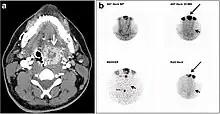

CT scan and scintigraphy images of lingular ectopic thyroid

An ectopic thyroid, also called accessory thyroid gland, is a form of thyroid dysgenesis in which an entire or parts of the thyroid located in another part of the body than what is the usual case. A completely ectopic thyroid gland may be located anywhere along the path of the descent of the thyroid during its embryological development, although it is most commonly located at the base of the tongue, just posterior to the foramen cecum of the tongue. In this location, an aberrant or ectopic thyroid gland is known as a lingual thyroid.[3] If the thyroid fails to descend to even higher degree, then the resulting final resting point of the thyroid gland may be high in the neck, such as just below the hyoid bone.[3] Parts of ectopic thyroid tissue ("accessory thyroid tissue") can also occur, and arises from remnants of the thyroglossal duct, and may appear anywhere along its original length.[3] Accessory thyroid tissue may be functional, but is generally insufficient for normal function if the main thyroid gland is entirely removed.[3]